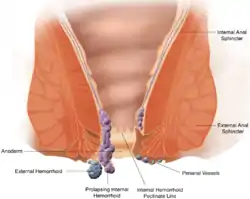

Hemorrhoids are visible blood vessels from the internal or external venous plexuses of the anus. Haemorrhoids may; cause bleeding after passing a motion; be painful; cause an itch; or prolapse out of the anus.[9] Haemorrhoids are often associated with straining due to constipation, and pregnancy.[9] Usually, haemorrhoids are managed with medications to make motions more soft and prevent straining during constipation. Some haemorrhoids require surgery to manage, which may involve placing a band around the haemorrhoid, in order for it to lose blood supply; or surgical excision.[9]

A grade IV hemorrhoid protrudes out of the anus.

A grade IV hemorrhoid protrudes out of the anus.